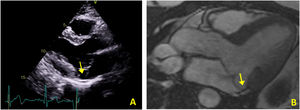

Case 2The second case is of a 34-year-old woman with no relevant personal or family history. She was referred for an arrhythmology consultation in 2014 due to non-sustained palpitations, without syncope. The 24-hour Holter revealed very frequent PVCs (16.4% of all beats), polymorphic but mainly monofocal, with LBBB morphology and superior axis, in bigeminy and trigeminy, with frequent doublets and triplets, as well as two episodes of non-sustained VT (maximum five complexes). The transthoracic echocardiogram showed the mitral valve with a myxomatous appearance and prolapse of both leaflets, causing mild mitral regurgitation, as well as MAD and preserved biventricular systolic function (Figure 3A). Laboratory tests revealed no abnormalities. CMRI revealed MVP with MAD and hypermobility of the basal segment of the inferolateral wall but no fibrosis (Figure 3B).